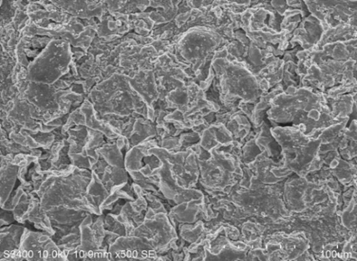

Scanning electron microscopy (SEM)

The surfaces and cross-section morphologies of the floating microspheres were observed using a scanning electron microscope (SEM) operated at an acceleration voltage of 25 kV. The microspheres were made conductive by sputtering thin coat of platinum under vacuum using Jeol JFC-1600 autofine coater and then the images were recorded at different magnifications. The formulation F3 was subjected to SEM studies.26

Surface characterization

Shape and surface characteristic of optimised formulation F3 Norfloxacin floating microspheres examine by scanning electron microscopy. The SEM result showed that the particle size of formulation was found to have regular and spherical shape with rough and uneven surface (Figure 5).

Figure 5: scanning electron microscopy for F3 represents different magnifications